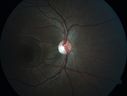

12 year old man. His vision was not correctable to 20/20. There was concern about macular disease. His was diagnosed with Streff syndrome in NY. Â

VA OD: Dcc20/63 PH20/50-2 NccJ2

VA OS: Dcc20/63 PH20/50-2 NccJ3

IOP: TP: OD:10 OS:15 Time:02:24 PM

His father and two of his fathers siblings have similar vision loss.

The diagnostic criteria for Streff syndrome are not well established, and the validity of this condition has not been recognized by The American Academy of Ophthalmology, The American Academy of Pediatric Ophthalmology, The American Academy of Optometry or The American academy of Pediatrics.     (0 votes)